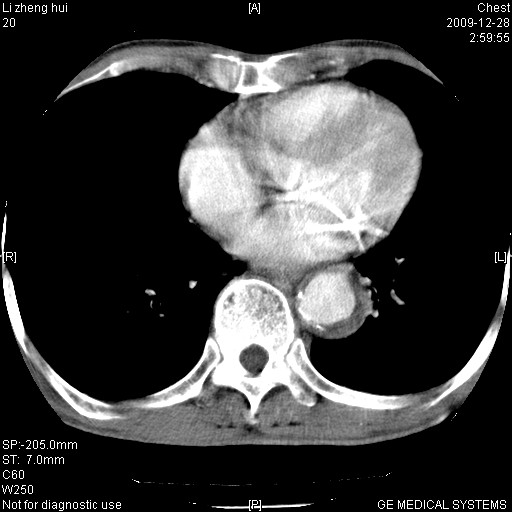

标题: CT23859:胸主动脉瘤

男  79岁 胸部痛急诊入院,晚上做的增强

考虑主动脉瘤?(增粗、钙化、壁血栓?)

动脉瘤伴附壁血栓

1)考虑胸主动脉壁间血肿或夹层动脉瘤。2)多发性肝囊肿。

1)考虑胸主动脉附壁血栓或夹层动脉瘤。2)多发性肝囊肿。